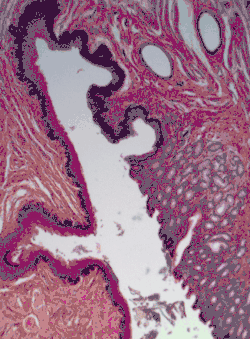

Плоский многослойный эпителий, окраска гематоксилин-эозин

В многослойных эпителиях с базальной мембраной связаны только клетки самого нижнего (базального) слоя. В многослойном плоском неороговевающем эпителии различают три слоя: базальный, шиповатый (промежуточный) и плоский (поверхностный). Клетки базального слоя кубические или призматические, среди них имеются стволовые клетки, сохраняющие способность к митозу; именно благодаря делениям этих клеток популяция эпителиоцитов восстанавливается, несмотря на постоянное отмирание поверхностных клеток эпителия. Шиповатый слой образован эпителиоцитами неправильной многоугольной формы. Клетки базального и шиповатого слоёв содержат хорошо выраженные пучки тонофиламентов кератина. Плоские клетки, образующие поверхностный слой эпителия, постоянно отмирают и отпадают с поверхности эпителия, однако, в отличие от роговых чешуек многослойного плоского ороговевающего эпителия, в них различимы ядра. Многослойный плоский неороговевающий эпителий покрывает роговицу глаза, выстилает ротовую полость и пищевод[33], а также влагалище[17] и покрывает настоящие голосовые связки[34]. Многослойный неороговевающий эпителий, содержащий множество одноклеточных слизистых желез, покрывает тело у круглоротых и хрящевых рыб[35].